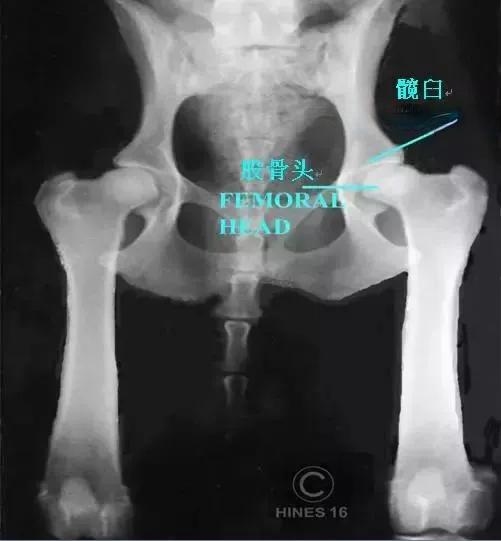

髋关节是连接大腿和骨盆的关键部位,承受着狗狗全身最大的重量。 它由球状的股骨头和碗状的髋臼构成,正常情况下两者应紧密贴合。然而,当这种结构无法完美匹配时,就会导致髋关节发育不良。随着狗狗的活动,松动的股骨头会与髋臼相互摩擦,造成骨骼磨损、炎症和疼痛。如果不加以干预,最终可能导致狗狗无法行走。